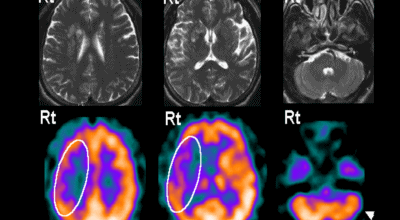

4. 뇌종양 초기증상 - 교모세포종의 문제

뇌종양 초기증상 여섯 번째는 교모세포종의 문제입니다. 가장 흔한 뇌종양은 수막종이며 종양의 크기나 위치에 따라 수술이 필요하지 않을 수 있지만 청각 신경초종은 이명을 나타나게 할 수 있고 심한 경우 안면 마비, 경련 및 통증을 유발할 수 있지만 뇌종양은 생존을 좌우하게되는 교모세포종 문제가 뒤늦게 생기는 것으로 주의가 필요한 이유입니다.